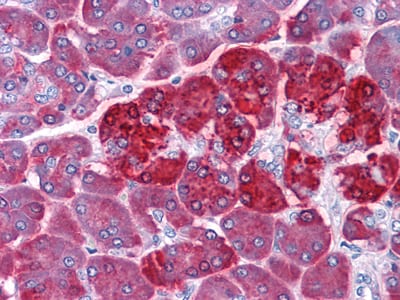

分类: 科研抗体货号: 20351别名: RPS27应用: IHC反应种属: Human